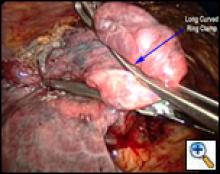

| Figure 3 |

Once the working incision has been made and the lung collapsed, further pressure on the upper lobe parenchyma with a tonsil sponge on a long curved ring clamp ensures complete collapse of the upper lobe. The mediastinal pleura around the upper pulmonary hilum is mobilized sharply or with cautery (Video 2). This allows for increased mobility of the upper lobe. A long curved ring clamp (Figure 3) introduced through the working incision is used to grasp the upper lobe at its apex and retract the lobe superiorly and laterally. This allows the surgeon to inspect the upper lobe and decide the position of the line of resection.